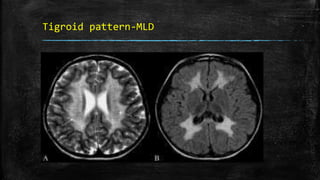

Tigroid pattern-MLD

• #97 Tigroid pattern. Axial T2W image of the brain in a child with metachromatic leukodystrophy shows symmetric, increased signal intensity of the white matter, with sparing of the subcortical U fibers. Linear low signal intensity areas radiating away from the ventricular margin (arrows) represent areas of white matter around the vessels that have been spared from the process of demyelination. These low signal linear areas within the hyperintense white matter resemble the skin of a leopard and hence the term ‘tigroid’ pattern. FLAIR axial MRI image (B) shows symmetric hyperintensity of the white matter sparing the subcortical U fibers